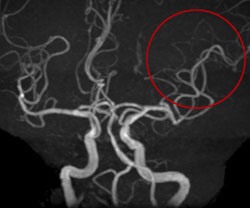

この症例は言葉が出ない、右手足が動かないという症状で救急搬送となった患者さんです。

左図のように向かって右側の血管が閉塞しており、t-PA療法を行いました。治療開始1時間後から劇的に症状は改善し、全く後遺症なく退院されました。

右図は治療後のMRA画像ですが、治療前は閉塞していた脳血管が開通しているのがわかります。